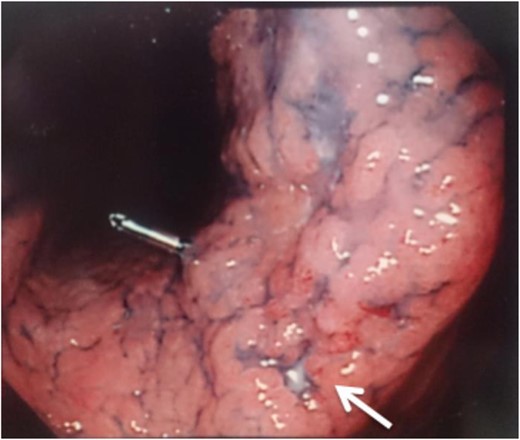

A 56-year-old man presented to our institution with esophageal and gastric cancer. Esophagogastroduodenoscopy (EGD) demonstrated a type 2 tumor occupying one-third of the circumference of the esophagus and measuring 28–33 cm from the incisors (Fig. 1). Endoscopy revealed that the tumor invaded the muscularis propria and biopsy revealed SCC. Moreover, a type 0-IIb tumor was located at the lesser curvature of the angle of the stomach. Endoscopy revealed invasion of the mucosa and biopsy revealed adenocarcinoma (Fig. 2). Computed tomography (CT) showed no enlarged lymph nodes in the mediastinum or distant metastasis in the liver or lung. Therefore, the patient underwent thoracoscopic esophagectomy (video-assisted thoracic surgery for esophagus), 2-field lymph node dissection, partial gastrectomy and gastric tube reconstruction via a retrosternal route for the advanced esophageal and early gastric cancers. Histopathologic analysis revealed Stage II (type 2, T3, ly2, v0, N0, PM0, DM0) esophageal and Stage I (type 0-IIb, T1, ly0, v0, N0) gastric cancer, with positive horizontal margins of dissection of the gastric cancer. Therefore, as additional treatment, we performed argon-plasma coagulation around the dissected gastric mucosa postoperatively.

A type 2 tumor occupying one-third of the circumference of the esophagus on esophagogastroduodenoscopy.